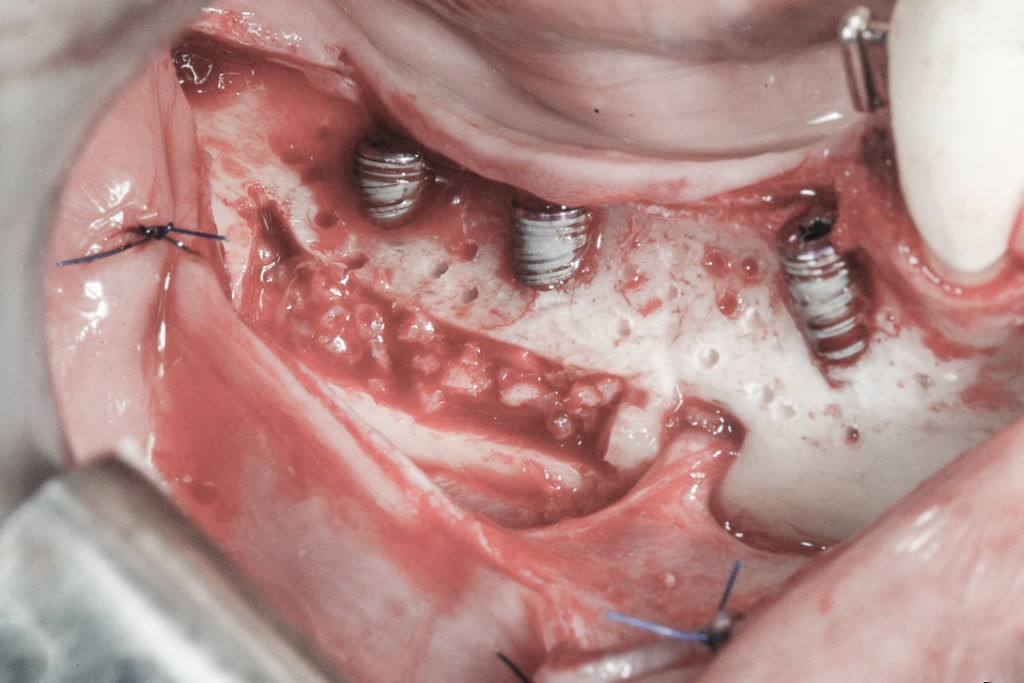

To kolejna metoda umożliwiająca precyzyjną odbudowę zadanego kształtu tkanki kostnej przy użyciu standardowych materiałów kościotwórczych, kości własnej lub PRF oraz zewnętrznego rusztowania w postaci siatki z biozgodnego stopu tytanu. Siatka jest indywidualnie projektowana w technologii CAD CAM i następnie drukowana dla konkretnego przypadku.

Dotychczas stosowane stabilizatory zewnętrzne w formie siatek tytanowych używane do regeneracji kostnej lub w zabiegach odtwórczych w chirurgii szczękowo-twarzowej uwzględniały materiały ręcznie doginane i formowane podczas zabiegu operacyjnego. Zastosowanie technologii CAD CAM dla potrzeb druku materiałów przeznaczonych do indywidualnej rekonstrukcji kostnej znacznie poprawiło precyzję i jakość uzyskiwanych efektów. Wdrożenie biozgodnych stopów tytanu do druku siatek zdecydowanie ograniczyło odsetek powikłań zapalnych.

Siatki stanowią stabilną obudowę – ograniczenie nadające kształt regenerowanej kości przy użyciu upakowanego pod nią materiału. Utrzymują i stabilizują rozdrobniony granulat kościotwórczy, co jest warunkiem prawidłowego procesu gojenia, jednocześnie nadając anatomiczny kształt i zakres odbudowie kostnej sprzed jej zaniku.

Precyzja projektu druku siatki bazuje na dokładności odwzorowania kształtu kości w stożkowej tomografii komputerowej CBCT, co zapewnia ich dobre przyleganie do podłoża kostnego oraz ogranicza powstawanie powikłań w postaci obnażania się siatek.

Precyzja projektu oraz materiał, z którego wykonana jest siatka (biozgodny stop tytanu), powodują, że obnażenie się siatki nie zaburza procesu gojenia i regeneracji kostnej. Wymaga jedynie większej ilości kontroli pozabiegowych oraz wzmaga czujność higieniczną zarówno ze strony lekarza, jak i pacjenta.

Ten rodzaj odbudowy kostnej stosowany jest w sytuacjach złożonych, trójwymiarowych 3D ubytków kości, przy których standardowe metody odbudowy są niewystarczające. Ilość kości, którą możemy uzyskać, stosując tę metodę, to nawet kilka centymetrów sześciennych.

Metoda rekonstrukcji kostnej w oparciu o indywidualnie drukowane siatki z tytanu dla implantacji wszczepów śródkostnych stosowana jest najczęściej jako dwuetapowa. W pierwszym etapie odbudowywana jest kość, natomiast implanty wszczepiane są po okresie 4–6 miesięcy. Na wgojenie implantów oczekujemy od 4 do 6 miesięcy w zależności od miejsca ich lokalizacji. Siatka tytanowa po spełnieniu swojej funkcji rusztowania dla odbudowującej się kości jest następnie usuwana w dniu wszczepienia implantu. Jeżeli kość spełnia odpowiednie warunki, istnieje możliwość zastosowania modyfikacji siatki tytanowej, która umożliwia jednoczesne wprowadzenie implantów wraz z odbudową kostną. Wariant ten skraca czas od pierwszego zabiegu do wykonania gotowych koron protetycznych na wprowadzonych implantach.